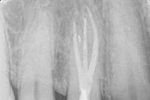

Revisionsbehandlung eines Unterkiefermolaren (37) vor geplanter Überkronung (Dr. Maik Göbbels) Download